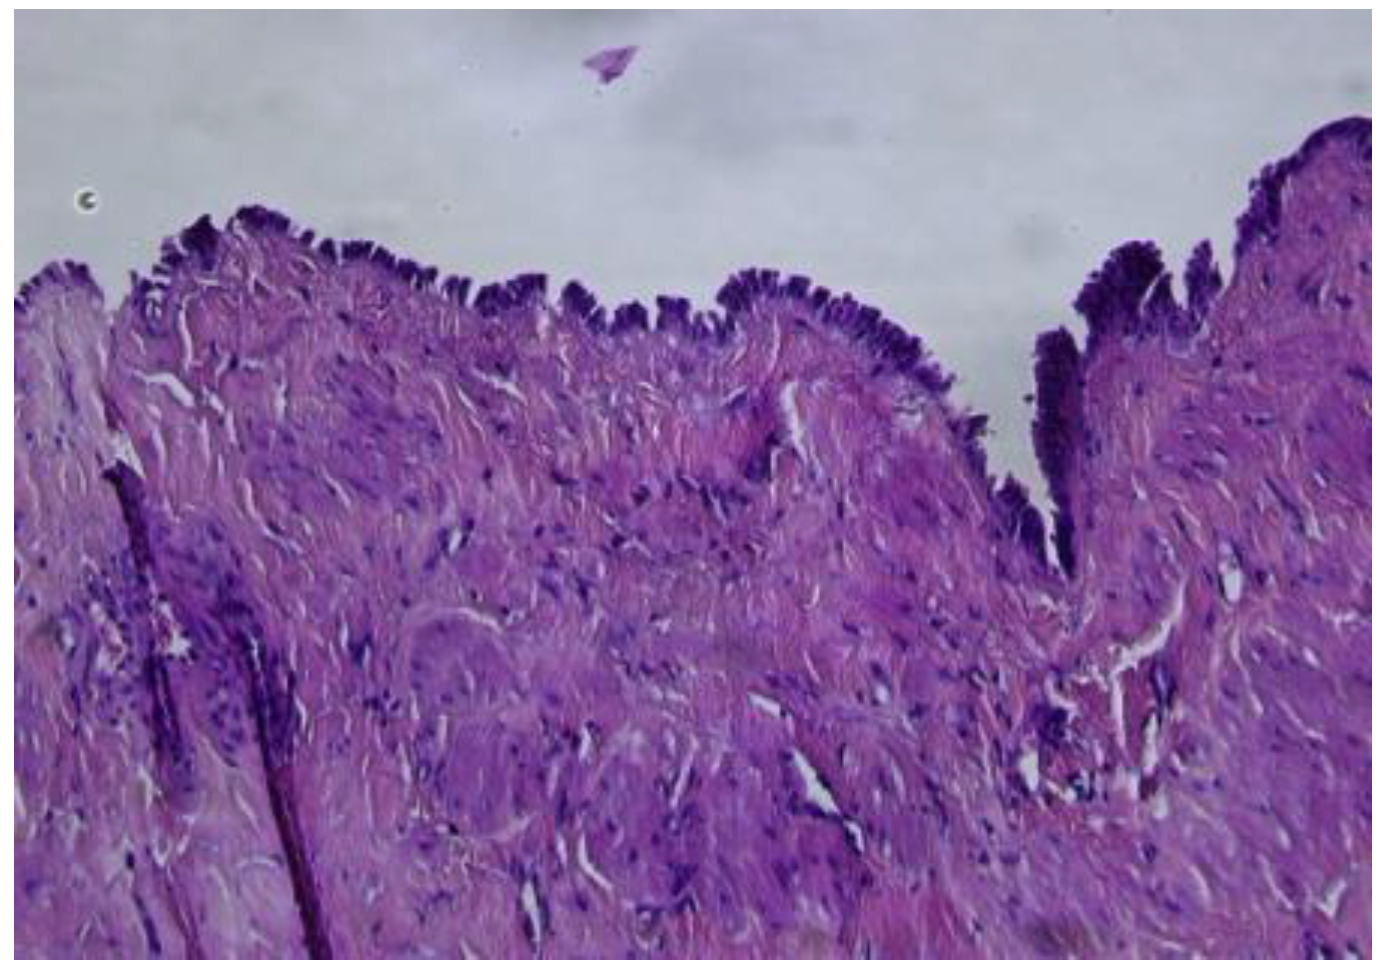

In the ovary, the microscopic exam revealed the second cyst, which was lined by a simple mucinous columnar epithelium, with focal glandular structures (Figure 7).

The epithelium presented isolated cuboidal to columnar cells with intracytoplasmic mucin and minor cytology atypia. The subjacent ovarian stroma presented luteinized areas, predominantly periglandular, accompanied by lymphoplasmacytic infiltrate, as well as rare calcifications. The remaining ovarian stroma presented follicles in different evolutive stages, atretic follicles, and a follicular cyst. Vascular ectasia was also observed.

Figure 7. Ovarian mucinous cystadenoma, lined by simple, mucinous columnar epithelium (HE ×10).